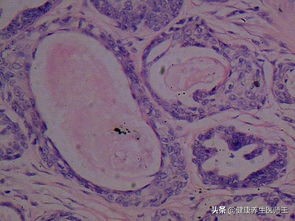

5、平滑肌瘤

平滑肌瘤 来源于外阴平滑肌、毛囊立毛肌或血管平滑肌。多见于生育年龄妇女,常位于大阴唇、阴蒂及小阴唇。质硬,表面光滑,突出于皮肤表面。镜下见平滑肌细胞排列成束状,与胶原纤维束纵横交错或形成漩涡状结构,常伴退行性变。治疗原则为肌瘤除术。